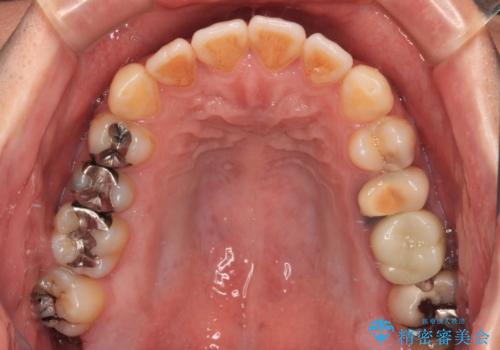

銀歯をなくしたい 全顎的なむし歯治療

- 銀歯やむし歯でものが挟まるところが気になるとのことで来院された患者様です。

左上の奥歯は神経が失活しており、根管治療が必要な状態でした。

その他は銀歯のインレー(部分的な詰め物)が装着されており、それらはむし歯を除去した後にセラミックインレーにて修復治療を行い、左下と根管治療を行う左上の奥歯はオールセラミッククラウンにて補綴治療を行うこととしました。